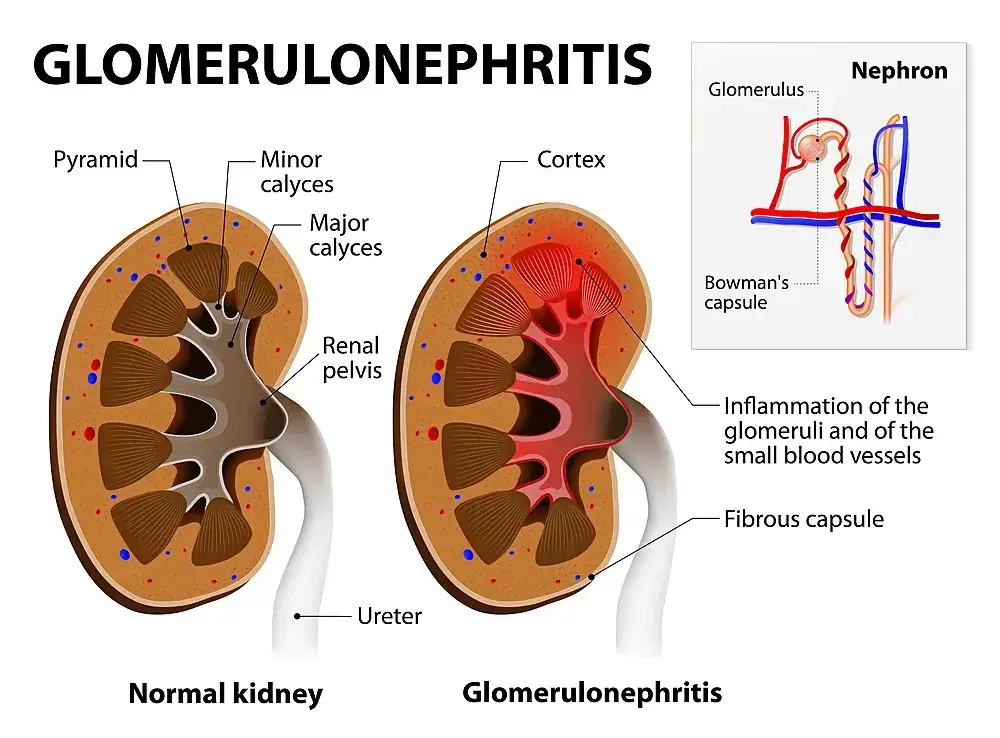

Glomerulonephritis

About 1 in every 3 will develop glomerulonephritis at some point in their lives. Glomerulonephritis can occur when the small blood vessels that supply blood to the kidneys become inflamed (called glomeruli).

This inflammation can damage the kidney’s filtering system, leading to serious health problems. There are many things you can do to prevent or reduce the chances of developing glomerulonephritis, including getting regular exercise, maintaining a healthy weight, and avoiding tobacco smoke.

This inflammation can damage the kidney’s filtering system, leading to serious health problems.